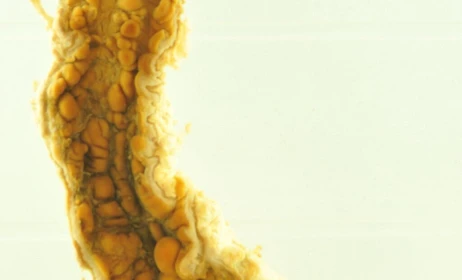

Για να επιβεβαιώσουν τον ρόλο της GIV, οι επιστήμονες πραγματοποίησαν πειράματα σε ποντίκια χωρίς αυτή την πρωτεΐνη. Τα ζώα παρουσίασαν συμπτώματα όμοια με εκείνα της νόσου Crohn, όπως σοβαρή φλεγμονή, πάχυνση του εντέρου και ουλές στους ιστούς. Μερικά εμφάνισαν ακόμη και σήψη, μια επικίνδυνη κατάσταση όπου η φλεγμονή εξαπλώνεται σε όλο το σώμα. Αντίθετα, ποντίκια με φυσιολογικά επίπεδα GIV κατάφεραν να αντιμετωπίσουν τα μικροβιακά ερεθίσματα χωρίς σοβαρές βλάβες.